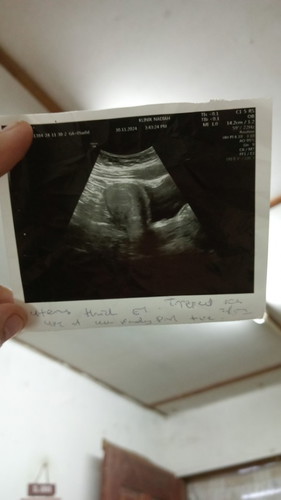

assalamualaikum saya meminta izin untuk bertanya, jika ad sesiapa yang sama/ tahu apa yang saya alami , usia kandungan masih awal 5 minggu, bru ni ada scan tapi x nmpk ap ii lagi, doc ckp peranakan cantik, sume ok, dinding rahim tebal, jadi situasi sy disini, ketika sy berjalan, mahu duduk/ bngun terasa ad sesuatu di blh kiri, x sakit cume rasa penuh, kadang ii nyeri di kawasan bawah perut,dan sakit pingng / tulang bontot, adakah normal ye ap yg saya lalui wahai ibu ii yang berpengalaman/ yg sama seperti saya #bantujawab #SeriusTanya #ingintahu #firstmom